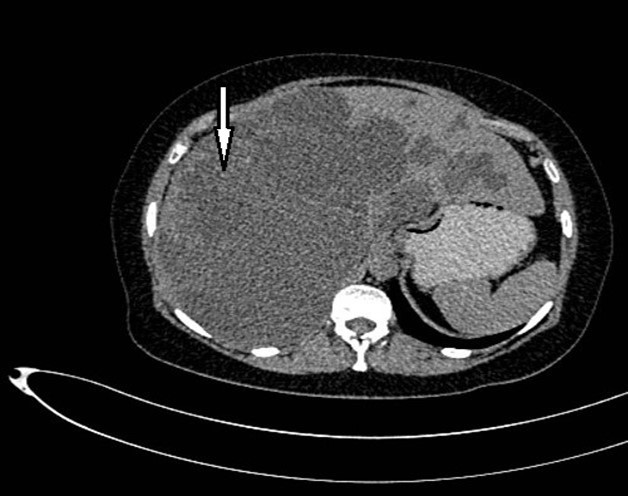

Abdominal tomography reported hepatomegaly secondary to polycystic disease and was reported with 3 cysts of greater size of 17, 14 and 12 cm in approximate diameter (Figure 1, Figure 2), kidney transplant without problems; the liver with mass effect on the stomach, the vena cava partially occluded, uncomplicated colon diverticulosis. Laboratory creatinine 1.44mg/dl urea 51.9 md/dl, glucose 71mg/dl, normal liver function tests.

Figure 1.Non-contrast CT shows hepatomegaly by multiple clusters of cysts.